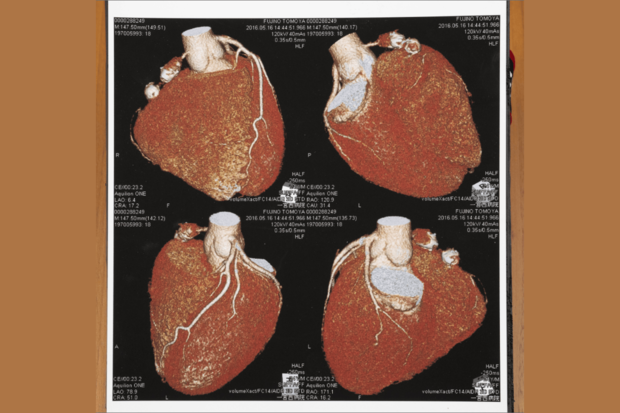

藤野さんの心臓画像。川崎病の後遺症で、心臓の上部の血管に動脈瘤がつながったソーセージのように残っている

[写真 3/15枚目] 藤野さんの心臓画像。川崎病の後遺症で、心臓の上部の血管に動脈瘤がつながったソーセージのように残っている